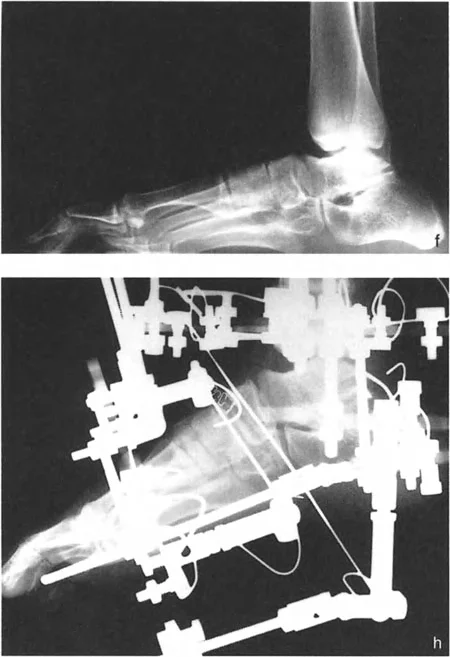

مبادئ بالي لتصحيح التشوهات

تُعد مبادئ الدكتور درور بالي حجر الزاوية في جراحة تصحيح تشوهات العظام. تركز هذه المبادئ على تحديد "مركز دوران التشوه" (CORA - Center of Rotation of Angulation) بدقة. إن موقع CORA يحدد كيفية تأثير التشوه على المفاصل المجاورة ويوجّه الجراح في اختيار مكان قطع العظم (Osteotomy).

• فهم CORA:

• إذا كان CORA قريبًا من مفصل الكاحل، فإن التشوه يؤثر بشكل أساسي على محاذاة الكاحل.

• إذا كان CORA قريبًا من مفصل الركبة، فإن التشوه يؤثر بشكل أساسي على محاذاة الركبة.

• إذا كان CORA في منتصف عظم الساق، فإنه يؤثر على كلا المفصلين ولكن بدرجة أقل.

• قواعد بالي لقطع العظم:

1. القاعدة الأولى: عندما يمر قطع العظم ومحور تصحيح الزاوية (ACA) عبر CORA، يتم تحقيق تصحيح زاوي نقي دون أي إزاحة.

2. القاعدة الثانية: عندما يمر ACA عبر CORA، ولكن قطع العظم يتم في مستوى مختلف (غالبًا ما يكون ضروريًا لتوفير مساحة كافية للتثبيت)، يتم تحقيق تصحيح زاوي نقي، ولكن أطراف العظم ستنزاح في موقع قطع العظم. يجب على الجراح توقع هذه الإزاحة وإدارتها.

3. القاعدة الثالثة: إذا كان ACA وقطع العظم في نفس المستوى، ولكن لا يمر أي منهما عبر CORA، فسيحدث تشوه إزاحة (ترجمة) غير مرغوب فيه. يتطلب هذا الأمر من الجراح إجراء إزاحة متعمدة للقطعة العظمية البعيدة أثناء التصحيح الزاوي لإعادة محاذاة المحور الميكانيكي.

أنواع جراحات قطع العظم فوق الكاحل (Supramalleolar Osteotomy)

جراحة قطع العظم فوق الكاحل (SMO) هي الإجراء الأكثر شيوعًا لتصحيح تشوهات قصبة الساق البعيدة. تتضمن هذه الجراحة قطعًا دقيقًا في عظم الساق (القصبة) فوق مفصل الكاحل مباشرة، ثم إعادة محاذاة العظم وتثبيته في الوضع الصحيح. هناك عدة أنواع من هذه الجراحة: